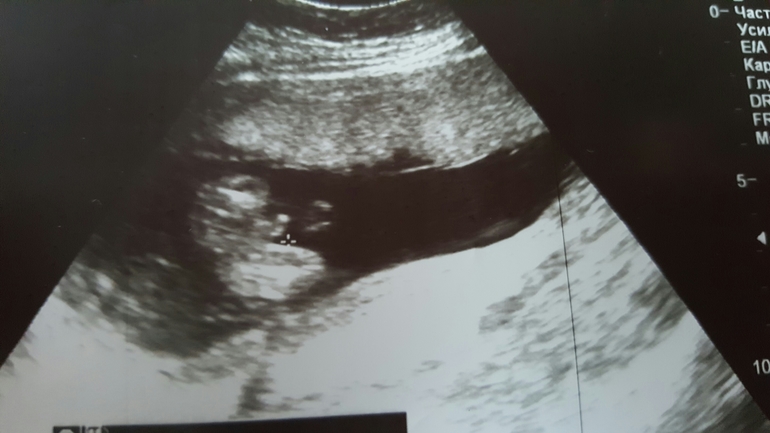

УЗИ после 2-х недельного кашля и пол подтвердили!!!

на узи все хорошо, сердечко бьется отлично, никаких угроз не обнаружено! И вроде подтвердили пол!! Я в радости!!!))))

Да мальчишка вроде, родится узнаем!!!)))))))